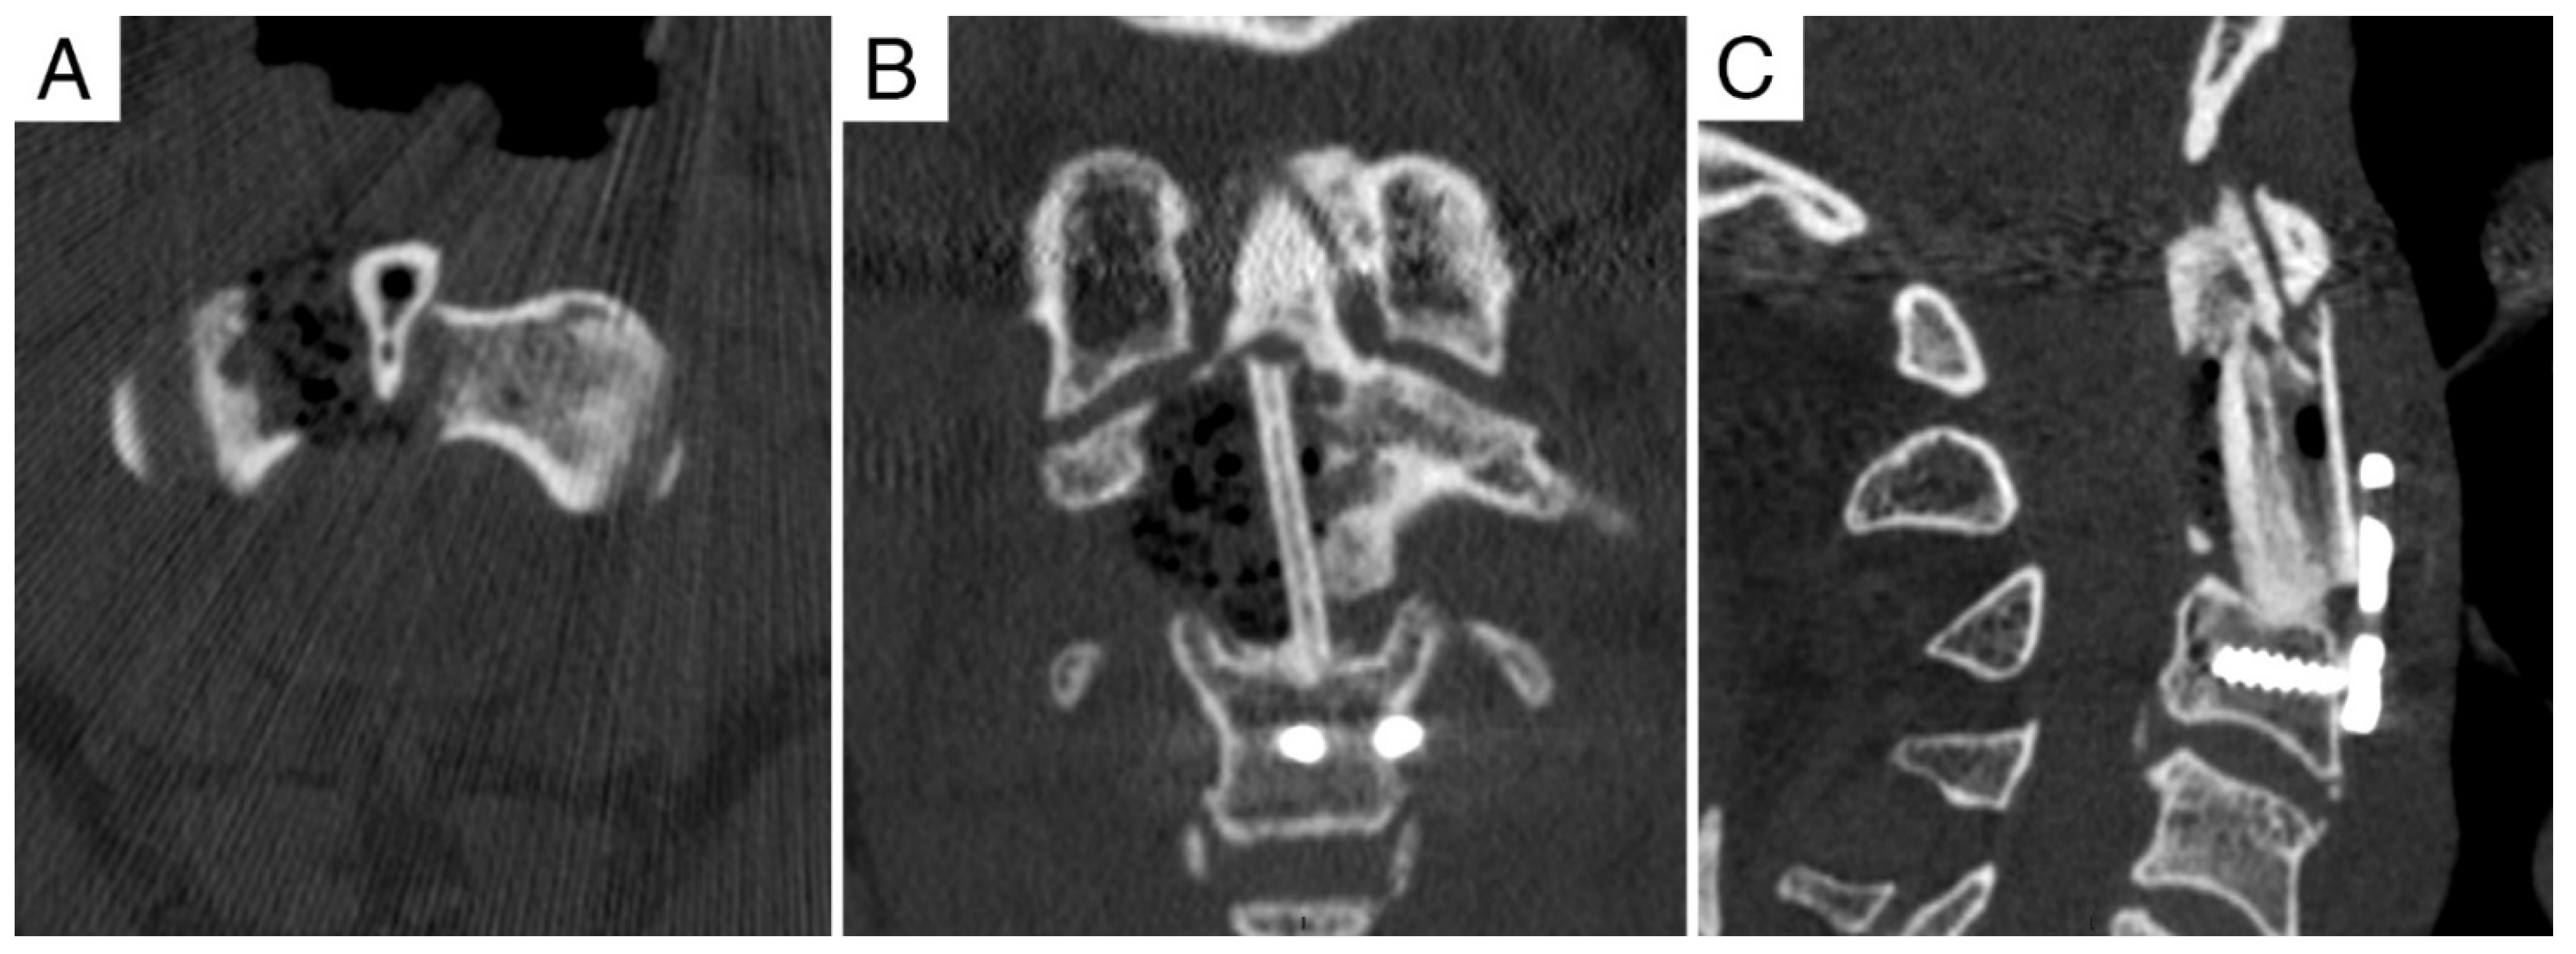

3.1. Case Report 1

| 1 | 65, M | Recurrent chordoma C2 | IB | 8-5/A-D | RT (70.4 Gy carbon-ion, Δt = 4 y) Extracapsular debulking and reconstruction w/ allograft and carbon-fiber buttress plate (Δt = 2 y) | A | Intralesional | 18 | 20 | DOC |